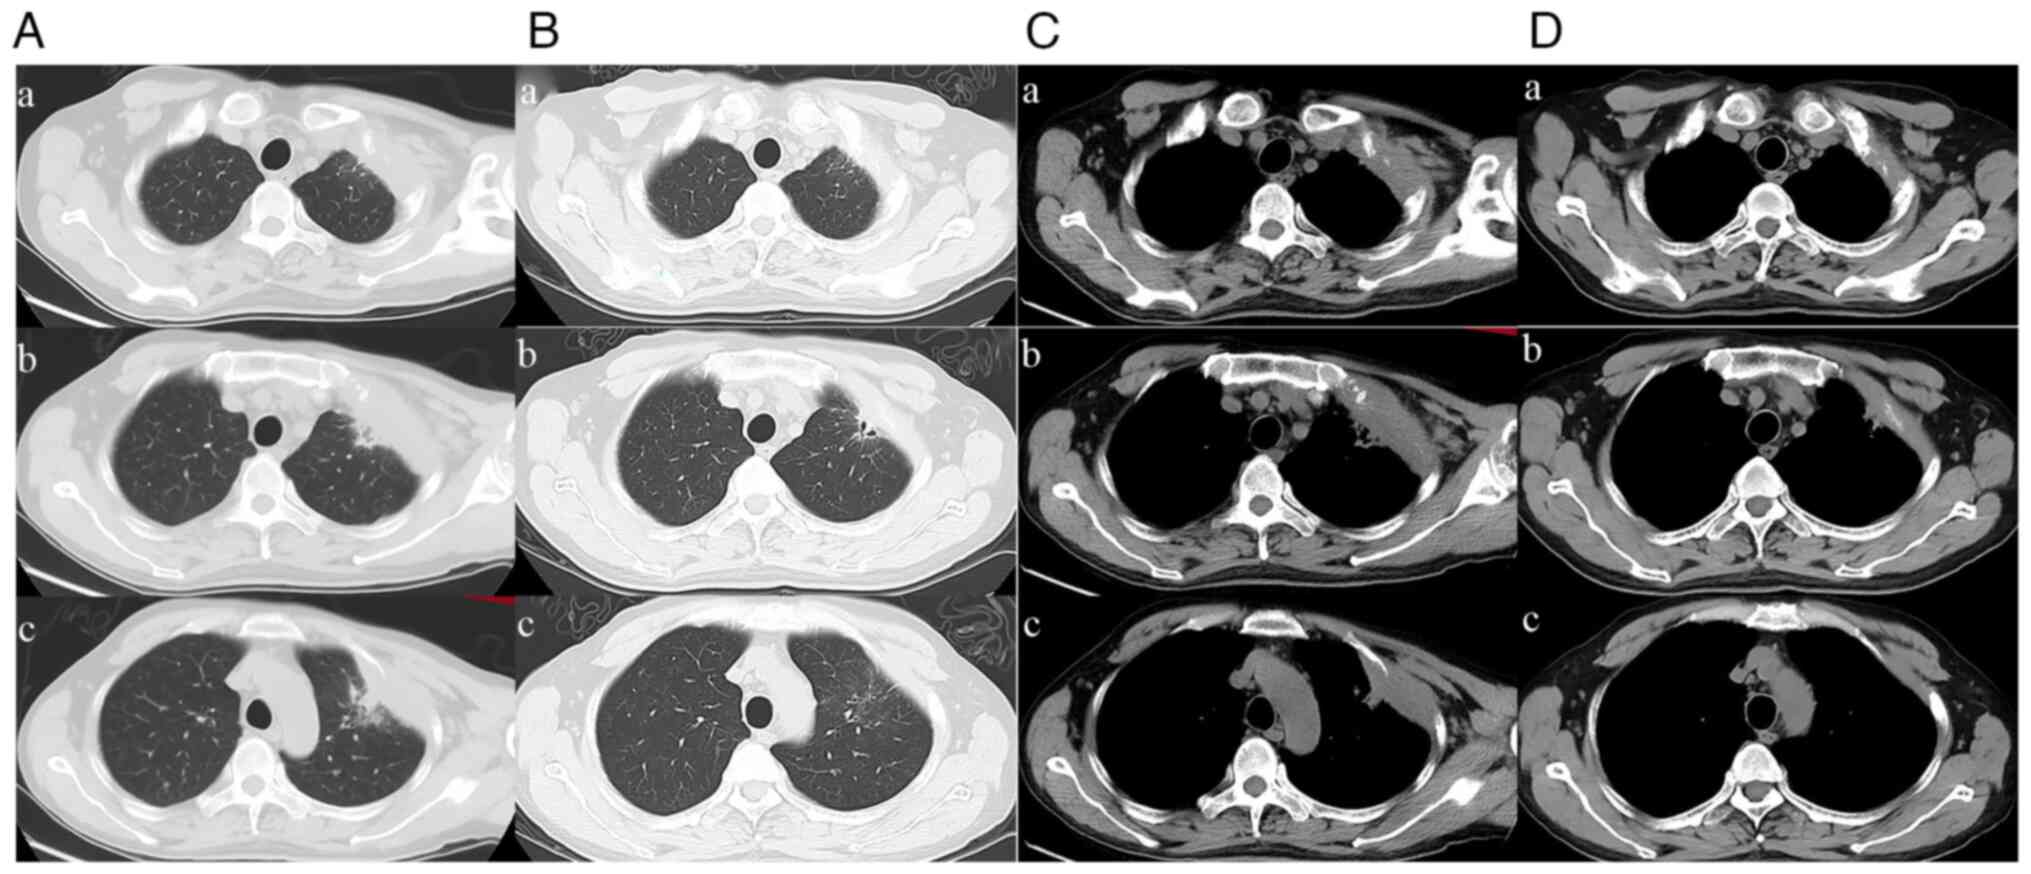

A superior pulmonary sulcus tumor, also known as a Pancoast tumor, invades tissues or organs at the entrance of the thorax, such as the brachial plexus, upper ribs, vertebrae, subclavian vessels and stellate ganglia. Induction concurrent chemoradiotherapy followed by radical surgical resection is the preferred treatment. The present study reported the case of a 52‑year‑old male who presented at Hubei Cancer Hospital, Tongji Medical College (Wuhan, Hubei) with left chest pain and an abnormal chest computed tomography scan showing a mass of 81x43 mm in the left upper chest wall that invaded the first, second and third anterior ribs. Biopsy of the mass showed stage cT4N0M0, IIIA, poorly differentiated adenocarcinoma and epidermal growth factor receptor+. The patient was treated by induction chemotherapy and targeted therapy, which was followed by surgical resection of the left upper lobe and the affected chest wall via the transmanubrial approach. The targeted therapy with almonertinib was continued postoperatively. To date, no disease recurrence has been detected during the 4 months follow‑up.

Figure 1

Figure 2

Figure 3